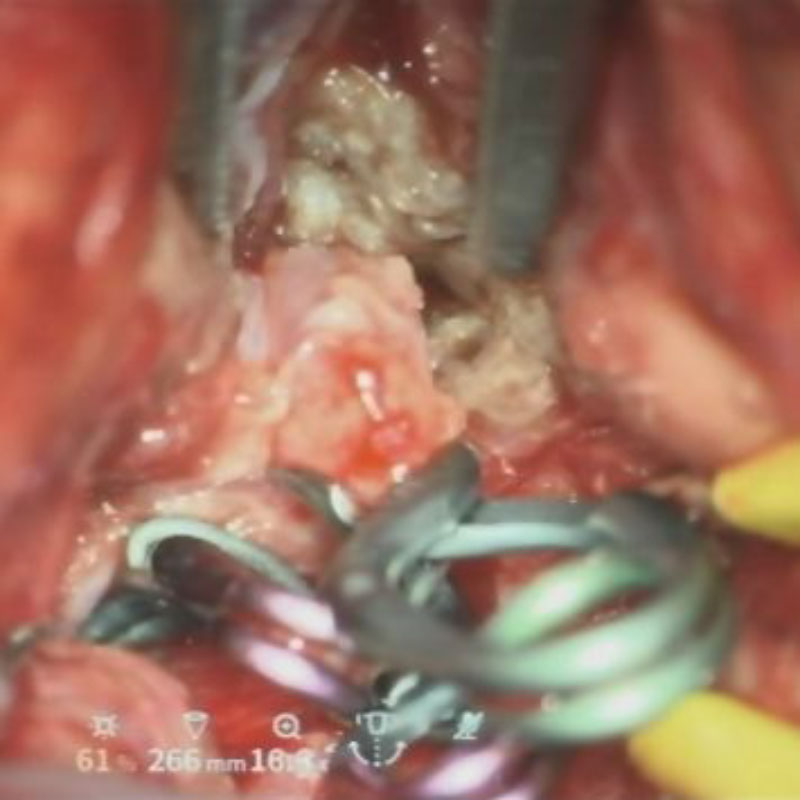

クリップ前

クリップ後